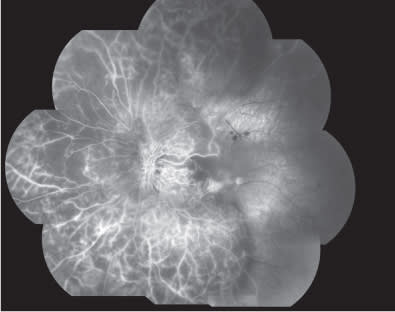

At baseline, best corrected visual acuity (BCVA) was 0.8 Snellen equivalent at right eye (RE) and 0.3 Snellen equivalent in the left eye (LE). Intraocular pressure was 14 mm Hg in both eyes. Slit-lamp examination of the anterior segment revealed nuclear sclerosis. Clinical examination of the retina revealed a nonproliferative diabetic retinopathy in both eyes, associated with the presence of clinically significant DME with hard exudative deposition in the LE (Figure 1). Central retinal thickness (CRT) on OCT was 223 μm and 551 μm in RE and LE, respectively, at baseline. Fluorescein angiography (FA) (Figures 2 and 3) disclosed more clearly the presence of the diabetic retinopathy with DME in the LE. The patient was advised to undergo intravitreal injection of ranibizumab.

Figure 2. Composite fluorescein angiography in the early phases showing a nonproliferative diabetic retinopathy.

Figure 5. Composite fluorescein angiography in the early phases showing a delayed optic disc and arterial filling with extensive retinal ischemia involving both posterior pole and periphery.